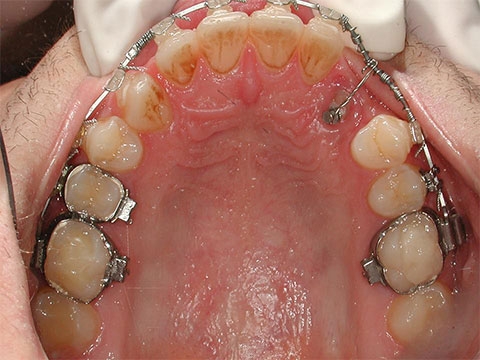

Si nota il sottile filo metallico che collega il bottone sul canino, con il resto dell'apparecchiatura ortodontica.

Guarita la piccola ferita chirurgica, si puo' ora cominciare a tirare il dente verso la sua posizione ideale